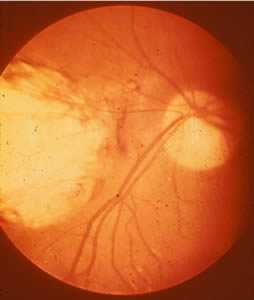

Ocular toxoplasmosis: Chorioretinitis.

Figure A: Severe, active retinochoroiditis.

Figure B: Peripheral retinochoroiditis.

Figure C: Central, healed retinochoroiditis.

Acquired infection with Toxoplasma in immunocompetent persons is generally an asymptomatic infection. However, 10% to 20% of patients with acute infection may develop cervical lymphadenopathy and/or a flu-like illness. The clinical course is usually benign and self-limited; symptoms usually resolve within a few weeks to months. In rare cases ocular infection with visual loss can occur. Immunodeficient patients often have central nervous system (CNS) disease but may have retinochoroiditis, pneumonitis, or other systemic disease. In patients with AIDS, toxoplasmic encephalitis is the most common cause of intracerebral mass lesions and is thought to usually be caused by reactivation of chronic infection. Toxoplasmosis in patients being treated with immunosuppressive drugs may be due to either newly acquired or reactivated latent infection.

Congenital toxoplasmosis results from an acute primary infection acquired by the mother during pregnancy. The incidence and severity of congenital toxoplasmosis vary with the trimester during which infection was acquired. Because treatment of the mother may reduce the incidence of congenital infection and reduce sequelae in the infant, prompt and accurate diagnosis is important. Many infants with subclinical infection at birth will subsequently develop signs or symptoms of congenital toxoplasmosis. Ocular Toxoplasma infection, an important cause of retinochoroiditis in the United States, can be the result of congenital infection, or infection after birth. In congenital infection, patients are often asymptomatic until the second or third decade of life, when lesions develop in the eye.